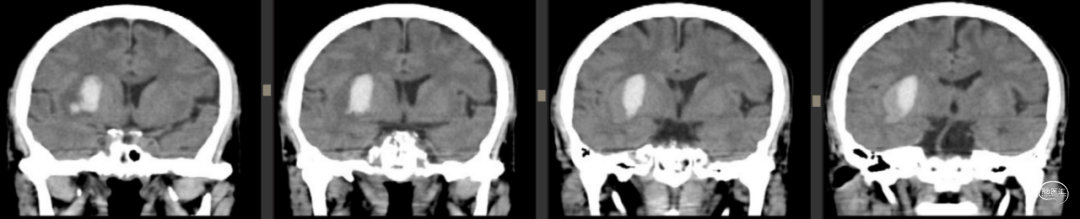

2023年7月28日

![]()

2023年7月30日